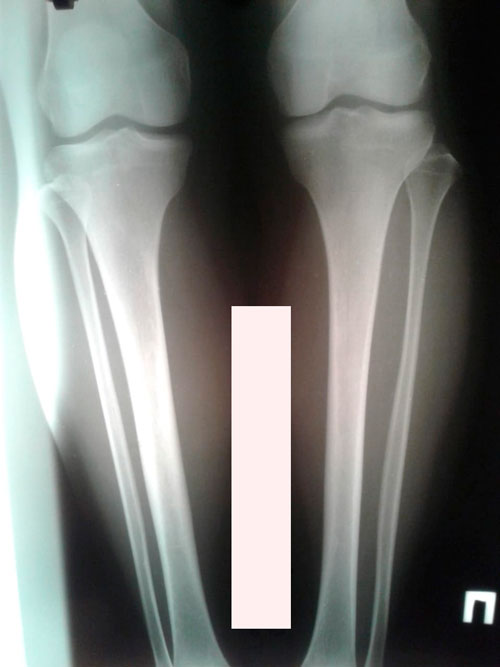

Исходник - 30 лет. Астана.

Дата операции - 07.03.2019г.

IMG_1663-06-03-19-10-24.JPG

IMG_1660-06-03-19-10-24.JPG